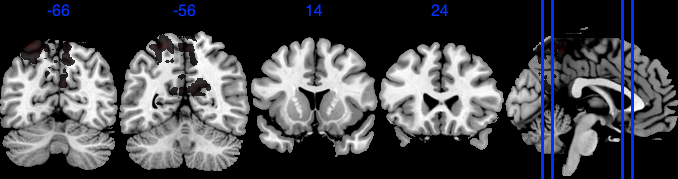

| Positive posterior mean of the spatial mediation effects (color range ) |

![]() |